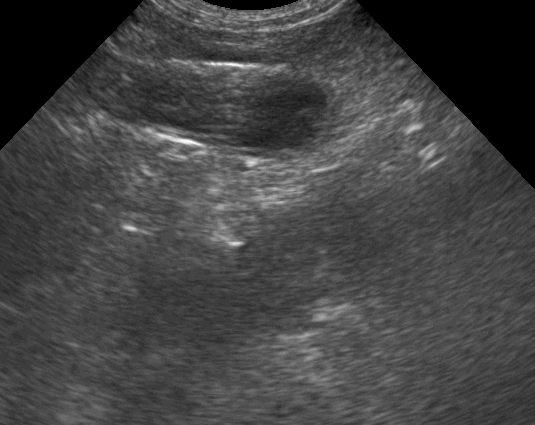

Findings: The ultrasound exam revealed a marked distention of a segment of the small intestine which ended in a narrowed lumen due to a thickened wall. The mesenteric lymph nodes were markendly enlarged and hypoechoic. A fine needle aspirate was performed.

The GIF shows the frames from the normal small intestinal layering to the thickened abnormal wall in a perpendicular view.